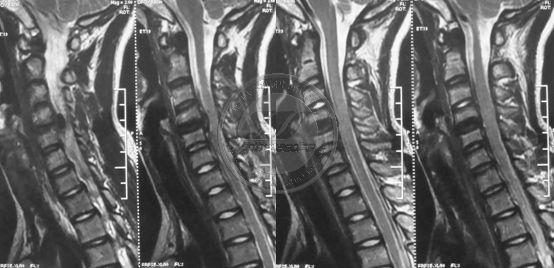

平山病的影像诊断

图片尺寸1080x810